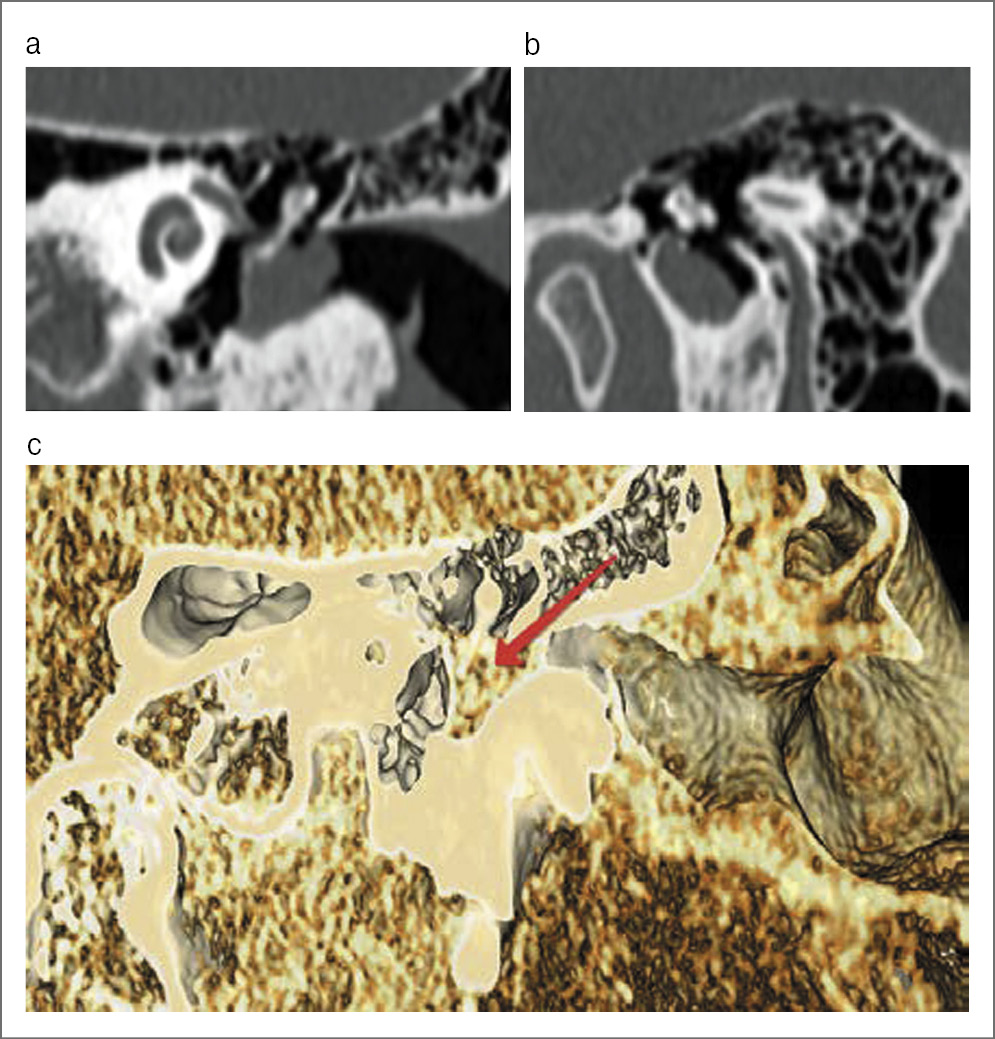

По данным КТ височных костей в барабанной полости имеется мягкотканное образование, окутывающее рукоятку и шейку молоточка (рис. 2).

Рис. 2. КТ височных костей: а – образование в барабанной полости окутывает рукоятку молоточка; b – сагиттальная проекция; с – 3D-реконструкция (стрелкой показано новообразование).

На КТ височных костей обычно в барабанной полости видна хорошо очерченная масса, без деструктивных изменений со стороны окружающей кости. По данным МРТ новообразование показывает низкую или среднюю интенсивность сигнала на Т1-ВИ, высокую интенсивность сигнала на Т2-ВИ и усиление сигнала после введения контраста. Новообразование может окутывать слуховые косточки, блокируя звукопроведение.